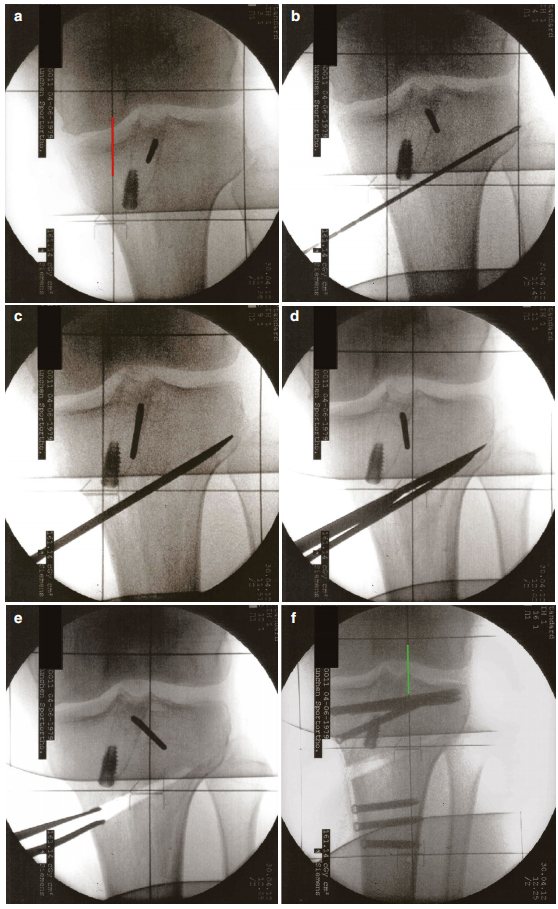

行横行截骨时,需将腘绳肌腱向远端牵开,并在透视引导下沿截骨平面插入两根平行导针,直至抵达外侧皮质(图6b)。导针于内侧约胫骨内侧平台远端4-5厘米处插入,向外上方斜行延伸,止于外侧平台远端约2厘米处。

胫骨结节截骨使用摆动锯完成(图5b)。必须确保对侧皮质完全截断,否则无法撑开横行截骨间隙。随后沿已置入的导针,用摆动锯进行横行截骨(图5c),并逐步插入多把骨凿将其撑开,直至距离外侧皮质约0.5-1厘米处(5d和6c, d);同时,在胫骨后方、沿横行截骨平面直接插入Hohmann拉钩,以保护后方的神经血管结构。截骨操作应在置入的导针下方进行,以最大限度降低胫骨外侧平台骨折的风险。外侧皮质应保持完整,以维持截骨部位的稳定骨桥。

图5 (a–f)采用远端指向额状面截骨并使用PeekPower HTO钢板(Arthrex)固定的双平面内侧开放楔形胫骨高位截骨术(HTO)。(a) 约8厘米长的前内侧纵行切口,起始于胫骨结节稍上方;(b) 胫骨结节的远端指向额状面截骨(截骨处可见锯片);(c) 沿(位于下方)已置入导针的轴向平面进行截骨;(d) 插入多把骨凿至距离外侧皮质约0.5–1厘米处;(e) 将截骨撑开器尽可能向后放置,逐步撑开截骨间隙;(f) 最终使用PeekPower HTO钢板(Arthrex)并在胫骨结节处加用两颗皮质骨螺钉完成固定。

图6 (a–f) 术中透视影像。 (a) 术前机械轴(红线);(b) 使用两根平行克氏针标记截骨平面;(c) 使用骨凿进行截骨直至外侧骨皮质前停止;(d) 置入多把骨凿;(e) 使用撑开器逐步撑开截骨间隙;(f) 使用PeekPower接骨板(Arthrex公司)固定截骨部位后的新机械轴(绿线)。

截骨长度可通过预先测量插入骨内导针的长度间接确定。完成后侧皮质的完全截骨至关重要,可避免在撑开截骨时出现显著的非预期后倾角增大。

随后使用截骨分层撑开器逐步撑开截骨至预定矫正目标,该撑开器应尽可能向后放置(图5e和6e)。通用原则是,若计划截骨后后倾角保持中立位,则截骨间隙后方的高度必须为前方的两倍。后倾角的变化可通过两根矢状位放置的斯氏针进行更精确的核查。

继而通过放射影像检查矫正程度。本方案推荐在患者腿下放置网格板以核查新机械轴(图6f)。亦可使用电刀线或对线杆作为替代方法。最终按说明使用角稳定钢板(如PEEK Power HTO Plate, Arthrex 或 TomoFix plate, Synthes)固定截骨(图5f)。若采用远端指向的额状面截骨,则需使用两颗双皮质皮质骨螺钉对胫骨结节骨块进行附加固定。